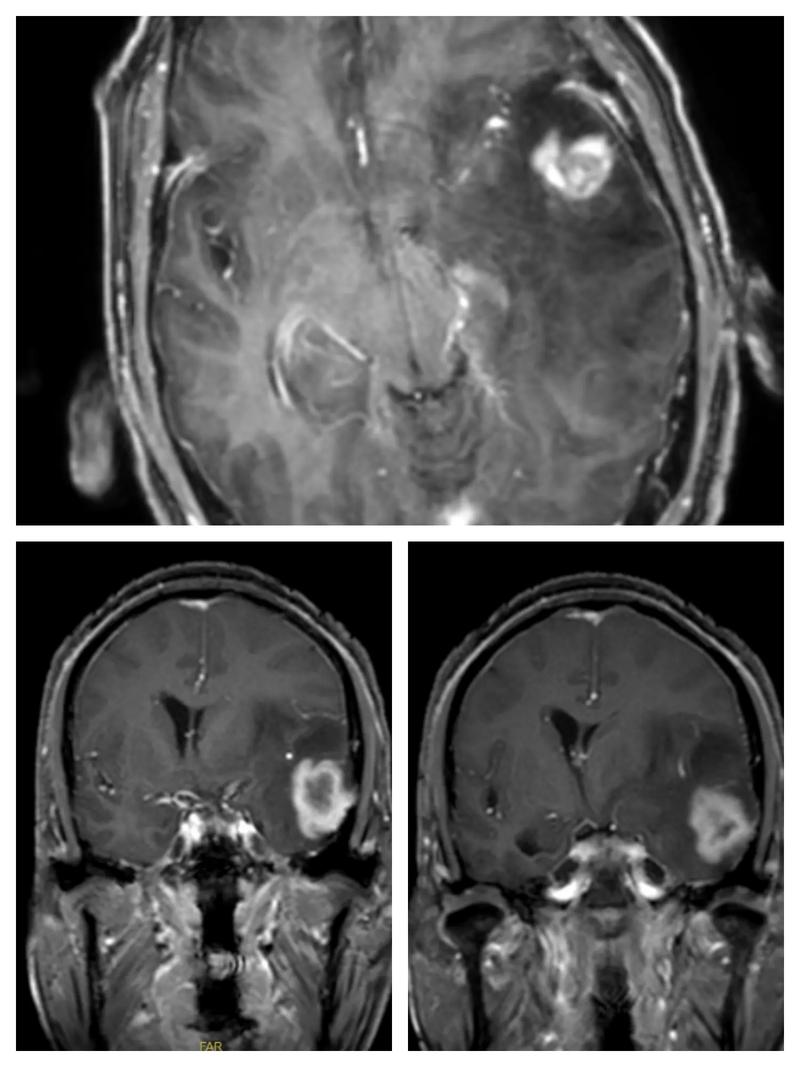

脑梗死的本质是脑组织因为缺血缺氧而发生坏死,MRI能够非常灵敏地捕捉到这种早期的病理变化,主要归功于以下几种特殊的成像序列:

- 表现: 发生梗死的区域在DWI上会显示为明显的高信号(亮斑),这个变化在脑梗发生后几分钟到一小时内就可能显现,比CT和常规MRI(T1、T2序列)要早得多。

- 意义: 只要DWI上没有看到明确的高信号,就可以非常有力地排除急性脑梗,这是医生判断是否为急性脑梗最关键的依据。

- 表现: 在发病几小时后,脑梗区域在FLAIR上也会显示为高信号,对于一些小的、陈旧的梗塞灶,FLAIR显示得比常规T2序列更清晰。